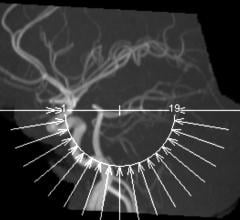

The Arthritis Foundation awarded $1 million to the Hospital for Special Surgery in New York City, University of California-San Francisco (UCSF) and Mayo Clinic in Rochester, Minn. to validate the use of new magnetic resonance imaging (MRI) techniques and newly identified biomarkers.